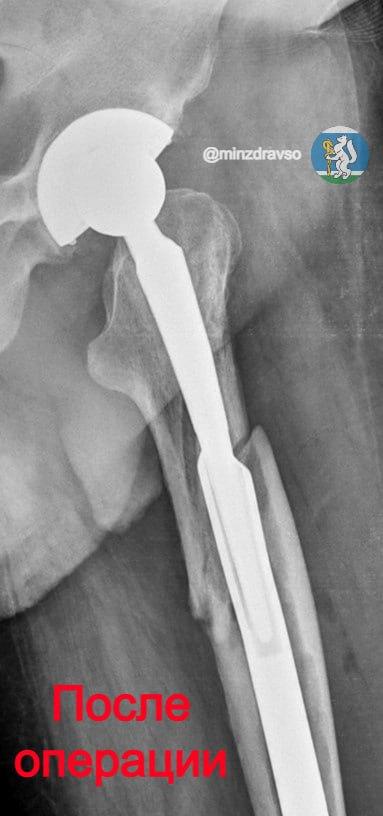

В Уральском институте травматологии и ортопедии имени В.Д. Чаклина совершили настоящий прорыв в лечении переломов вокруг эндопротезов бедра — одной из самых сложных проблем современной ортопедии. Медики разработали технологию интрамедуллярного ретроградного остеосинтеза, которая не имеет аналогов в России. По новой технологии в УИТО прооперировали более 200 пациентов.

«Суть метода — в ювелирной точности и индивидуальном подходе. Перед операцией врачи тщательно планируют каждый шаг по рентгеновским снимкам, затем для пациента изготавливают специальные стержни, которые надёжно фиксируют протез. Вмешательство проводится малоинвазивно: стержень вводится с обратной стороны, что позволяет пациенту практически сразу опираться на прооперированную ногу. Для восстановления анатомии созданы уникальные устройства, а для безопасного удаления старого цемента — специальный инструмент, который не повреждает кость», — сообщили в минздраве региона.